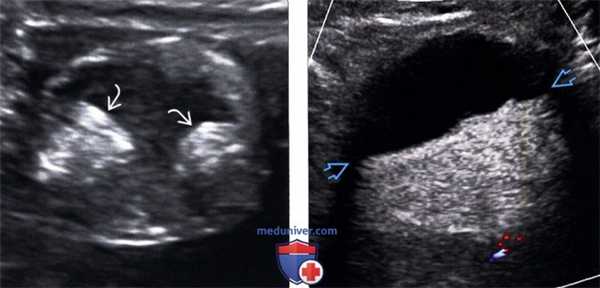

(Слева) На ультрасонографии определяются два узла Рокитанского в жире дермоида, имеющего противоречиво кистозный вид.

(Справа) На цветовой допплерографии определяется плавающий полутвердый - полужид -кий жир в дермоиде, жидкостно-жировой уровень.

(Слева) Трансвагинальная ультрасонография: отмечается, что дермоид может иметь нехарактерную картину визуализации на ультрасонографии при условии, что мягкотканный компонент будет преобладать над жировым. Данный дермоид гетерогенно эхогенный и заполняет замкнутое пространство кзади от матки.

(Справа) КТ с контрастированием того же образования, аксиальный срез: определяется относительно небольшое количество жира с преимущественно мягкотканным компонентом, что формирует специфичную картину визуализации на ультрасонографии.